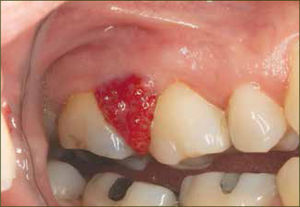

Gingivitis y embarazoLa gingivitis del embarazo (figura 1) es una inflamación proliferativa, vascular e inespecífica con un amplio infiltrado inflamatorio celular.

Clínicamente se caracteriza por una encía intensamente enrojecida que sangra con facilidad, engrosamiento del margen gingival e hiperplasia de las papilas interdentarias, que pueden dar lugar a la formación de pseudosacos periodontales. Las zonas anteriores y los sitios interproximales generalmente se ven más afectados (11) (figura 1).